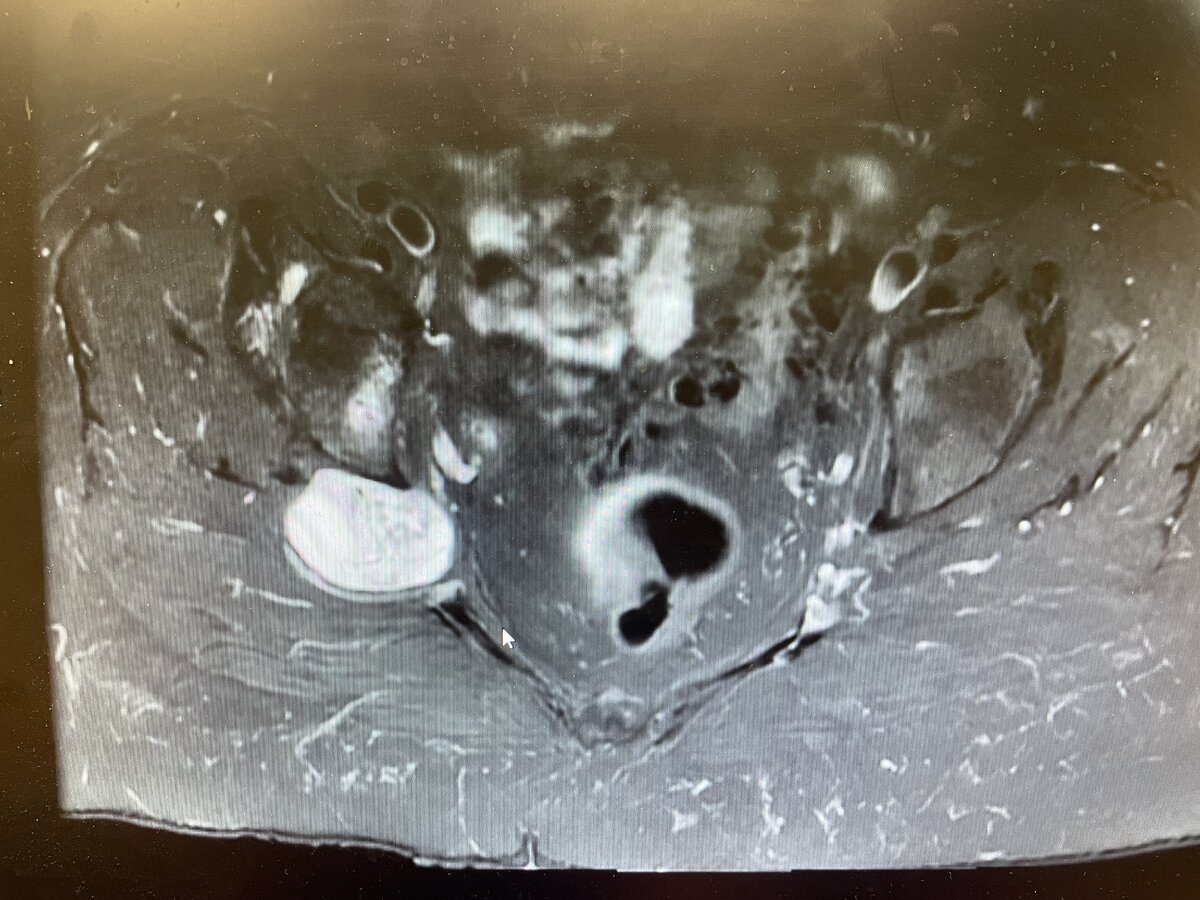

I have a patient coming in with a biopsy proven schwannoma of the greater sciatic foramen. It measures 4.7 x 3.6 x 3.2 cm and is symptomatic. How would you treat something of this size/location assuming surgery is not an option.

Pt is in her mid 70's with an ECOG of 0 to 1. Pt presented with issues of pain presumably due to the mass but otherwise neurologically intact with no weakness.